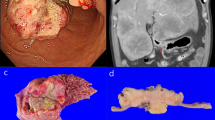

With the aid of a variety of cancer models, spanning from conventional in vitro [i.e., bidimensional (2D) cell monolayer] cultures to in vivo (i.e., animal) models, which represent crucial elements in the effective development of novel therapeutics in the laboratories around the world, the field of cancer biology has gained tremendous research advancement over the past few decades. In recent years, three-dimensional (3D) cell cultures have provided novel research opportunities with respect to traditional methods, by enabling the investigation of cancer in a realistic (i.e., higher complexity) environment, with tumor cells developing as seen in vivo [44]. For quick drug screening, fundamental cancer research and cancer diagnostics, 3D cell culture models function as less expensive and for many aspects better reliable platforms than animal models [45]. In time, many 3D culture systems are getting available, encompassing the simplest spheroids (i.e., cellular aggregates), tumor organoids or tumoroids (i.e., from patient’s cells), 3D organs-of-chip (i.e., using microfluidics), up to tissue engineered cancer constructs (i.e., using a biomaterial scaffold for cancer cell growth) [44]. The latter in vitro models take advantage of the multi- and inter-disciplinary knowledge built by the tissue engineering field for normal tissue/organ regeneration over the last 3 decades and can be built with an ideally infinite complexity by including different cell types, including immune cells, and ECM features, such as architectural, biochemical and mechanical cues [45]. These 3D platforms thus demonstrate versatility and customizability to reproduce the complexity and heterogeneity of TMEs in different cancers, which could be applied to sinonasal settings (Fig. 3).

Schematic representing the process of obtaining primary cells line from a patient for personalized medicine to allow the search for new molecular targets or the study of new drugs. Tumor tissue can be obtained from various clinical situations including surgery, endoscopy or needle aspiration. Primary culture should be isolated using specific protocols and monitoring what is isolated. The use of 3D models, in which the primary cultures are seeded, reproduces the TME, thus providing optimal conditions. This can be used for customized therapy or research into new targets. [Image sketched by the authors]

Noticeably, in regenerative tissue engineering, the biology of the target (i.e., healthy and functional tissue/organ) is much better known than in cancer tissue engineering, where tumor biology itself is a still quite unveiled subject of study. As such, the comparison with the molecular and histological features of the tumor specimens remains the only route for any meaningful investigation [44, 46•, 49]. The limiting factors hampering 3D in vitro models of sinonasal cancers to come into action are the small number of primary cell lines that have been isolated, along with the rarity and heterogeneity of sinonasal tumors. In the last decade, researcher groups have put efforts to synergize and obtain primary cell lines of various rare sinonasal tumors of the nose, by making an ITAC cell line available [53]. However, to the best of our knowledge, none long-lasting cell line of SMARCB1-deficient sinonasal carcinoma has been established so far. We have recently succeeded in isolating a cell line from a patient diagnosed with SNUC, located in the right maxillary sinus with negative INI-1 immunohistochemical determination (i.e., SMARCB1-deficient carcinoma) [54]. Isolation was performed using a new, optimized protocol and several steps were necessary leading to a cell culture, in which the phenotypic characteristics of the original tumor were found (Fig. 4).

Isolation of the primary culture of a sinonasal tumor from a patient diagnosed with SNUC, located in the right maxillary sinus with negative INI-1 immunohistochemical determination (i.e., SMARCB1-deficient carcinoma) [54]. The study was approved by CEAVNO Regional ethics committee, Pisa, Italy; approval number 17455 of June 25, 2020. A, B Histologic features of the tumor at diagnosis: A Hematoxylin and Eosin, and B immunohistochemistry of INI-1, where negativity is largely observed. C Primary cell culture under inverted light microscopy at passage 20. D, E Immunofluorescence characterization of the cell line, nuclei in blue with 4′,6-diamidino-2-phenylindole (DAPI): D Pan-CKs in yellow; E EZH2 protein in green and INI-1 (absent) in red. [Original images of the authors]

The culture was stable, delicate with a good growth rate, until passage 22, when it started declining. Succeeding in establishing SWI/SNF-deficient sinonasal cancer cell lines would be a turning point for building new 3D in vitro models of sinonasal cancers and studying such a sinonasal pathology at an improved level.